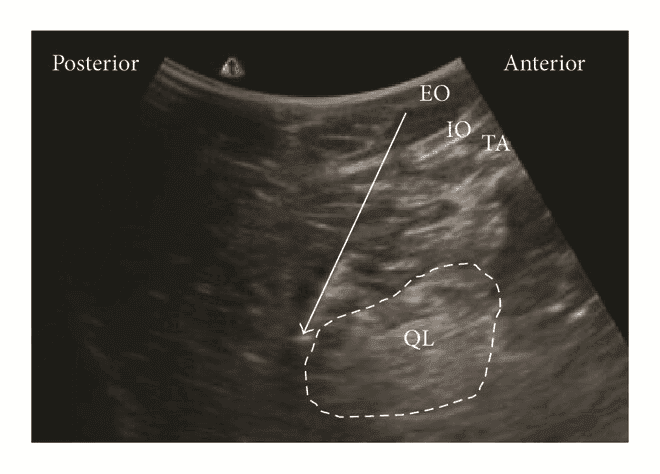

Для блокади QLB тип 1 лінійний датчик розміщують в поперечній площині по середньоаксилярній лінії, і переміщують назад доти, поки m. quadratus lumborum не стане видимим. Голку вводять in-plane з переднього або заднього краю датчика і просувають до моменту, коли вона пройде апоневроз поперечного м’яза живота, і її кінчик досягне простору між латеральною поверхнею m. quadratus lumborum та fascia transversalis. Місцевий анестетик вводять між апоневрозом і fascia transversalis біля латерального краю квадратного м'яза попереку.

Задня QL-блокада (тип 2 QLВ, QLB2)

Для QLВ2 конвексний/лінійний датчик розташовують в поперечній площині по середньоаксилярній лінії та зміщують назад, як і при QLB1, доки не стане видимим задній край квадратного м'яза попереку. Голку вводять in-plane з латеральної сторони датчика до моменту, коли її кінчик опиниться біля заднього краю m. quadratus lumborum. Місцевий анестетик вводять в середній шар тораколюмбальної фасції поблизу поперекового міжфасціального трикутника (LIFT). Правильне розміщення кінчика голки має призвести до поширення місцевого анестетика вздовж середнього шару fascia thoracolumbalis до паравертебрального простору.